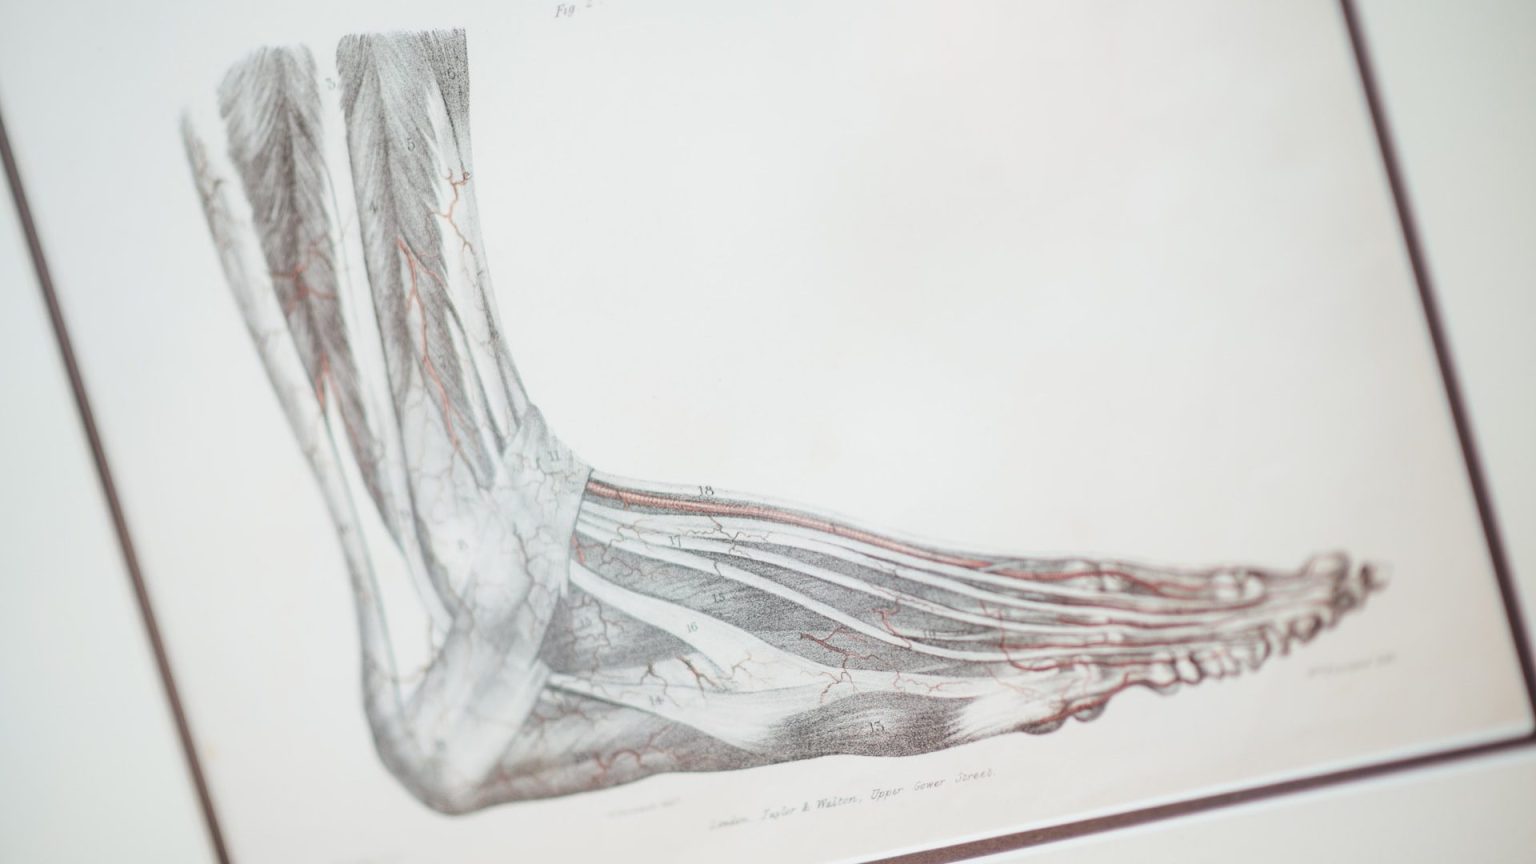

A new study finds evidence that not only are humans continuing to evolve, but we may be doing so at a faster rate than seen before. The research cites several examples of rapidly emerging traits such as an increasing lack of wisdom teeth, the shortening of babies’ faces with smaller jaws, the increased presence of a fabella (the small bone in the back of the knee joint) and extra bones in the feet.

The report’s primary focus, though, is a sudden increase in the appearance of the median artery in the adult human forearm.

The median artery supplies blood to a fetus’ forearm in the womb during early gestation. It typically atrophies and is replaced by the radial and ulna arteries before birth. Few adults have historically had all three arteries — median, radial, and ulna — but this has been changing.

The phenomenon was first noticed in the 18th century, and a study of the artery’s persistence was conducted in 1995. The more recent study extends that work, finding that the occurrence of the artery trio is accelerating.